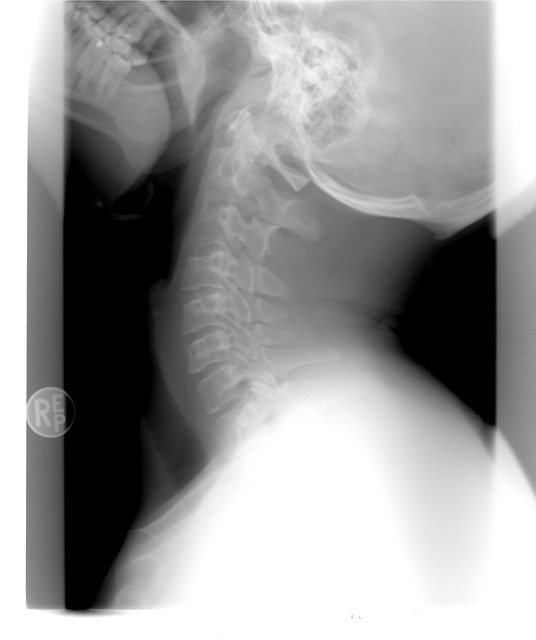

뒷목의 뻐근함은 때로는 심각한 건강 문제의 초기 증상일 수도 있습니다. 경추 탈출증, 요추 디스크, 혹은 자율신경계의 이상으로 인해 뒷목의 근육이 긴장되거나 압박을 받을 경우에도 뻐근함이 생길 수 있습니다. 이런 경우에는 전문가의 진단과 적절한 치료가 필요할 수 있습니다.